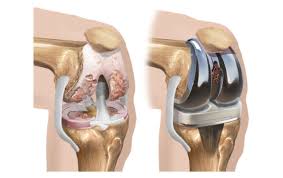

Total knee replacement (TKR) is a surgical procedure in which the damaged or worn-out surfaces of the knee are removed and replaced with components made of metal and plastic. These man-made components mimic the natural movement of a healthy knee, thereby relieving patients from pain, stiffness, and functional limitations.

- Removal of Damaged Surfaces: Using precise surgical tools, the surgeon cuts away the worn-out cartilage and bone from the femur (thigh bone), tibia (shin bone), and underside of the patella (kneecap). Special jigs and instruments help maintain correct alignment.

- Implantation of Prosthetic Components: The surgeon places metal caps on the femur and tibia, sometimes with bone cement. A plastic spacer is also inserted between them to allow smooth gliding. If needed, the back of the kneecap is also resurfaced with a plastic implant.